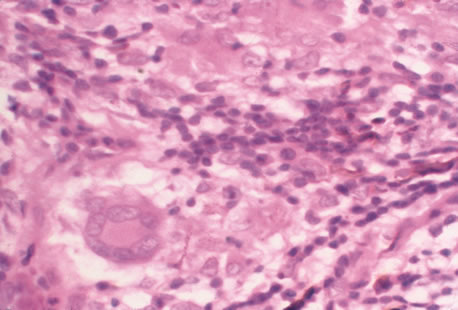

Any cell type may be infected, appearing larger than normal (cytomegalic) and demonstrating eosinophilic intranuclear “owl's eye” and smaller intracytoplasmic viral inclusion bodies, which are better seen with Giemsa or Papanicolaou's stains (Fig. 8). Histologic examination of tissue specimens, including bronchoalveolar lavage fluid and urine, may be useful for diagnosis.

|